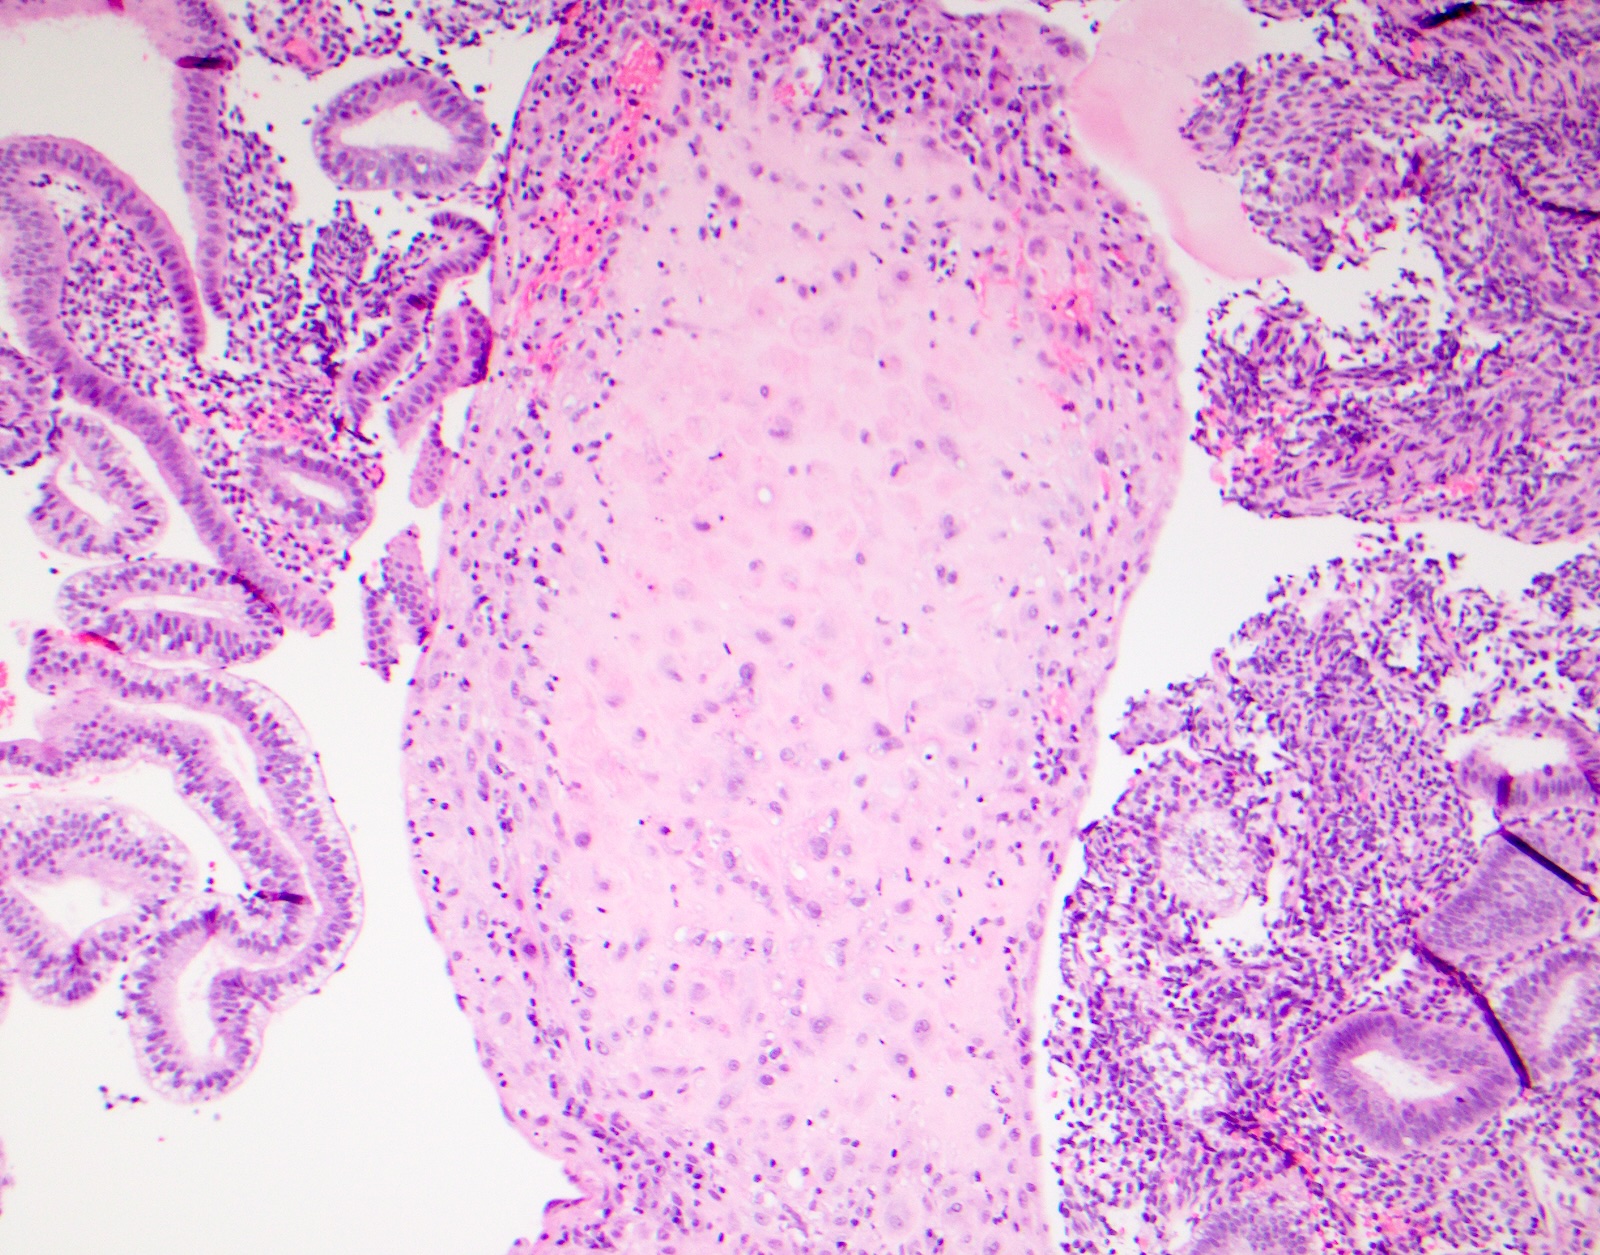

Microscopic (histologic) images

Contributed by Surekha Bantumilli, M.D. and Dimitri G. Trembath, M.D., Ph.D.

Positive staining - normal

- Prostate basal cells, skin (J Exp Clin Cancer Res 2003;22:441)

- Identification of the basal cell layer in prostate tissue in the determination of carcinoma

Practice question #1

A 65 year old man presents with elevated prostate specific antigen (PSA) and undergoes a prostate biopsy, stained with high molecular weight cytokeratin (HMWCK) (shown above). What is the most likely interpretation of this staining pattern?

- Benign prostate tissue

- Benign seminal vesicle

- High grade prostatic intraepithelial neoplasia

- Prostatic adenocarcinoma

- Urothelial carcinoma

Practice answer #1

A. Benign prostate tissue. The basal layer of benign prostate glands will stain with high molecular weight cytokeratin. Answer D is incorrect because staining will be lost on prostatic adenocarcinoma. Answer C is incorrect because high molecular weight cytokeratin staining can be present in high grade prostatic intraepithelial neoplasia but is not diagnostic by itself for this entity. Answers B and E are incorrect because the glandular appearance outlined by the high molecular weight cytokeratin staining is not consistent with either seminal vesicle or urothelial carcinoma.